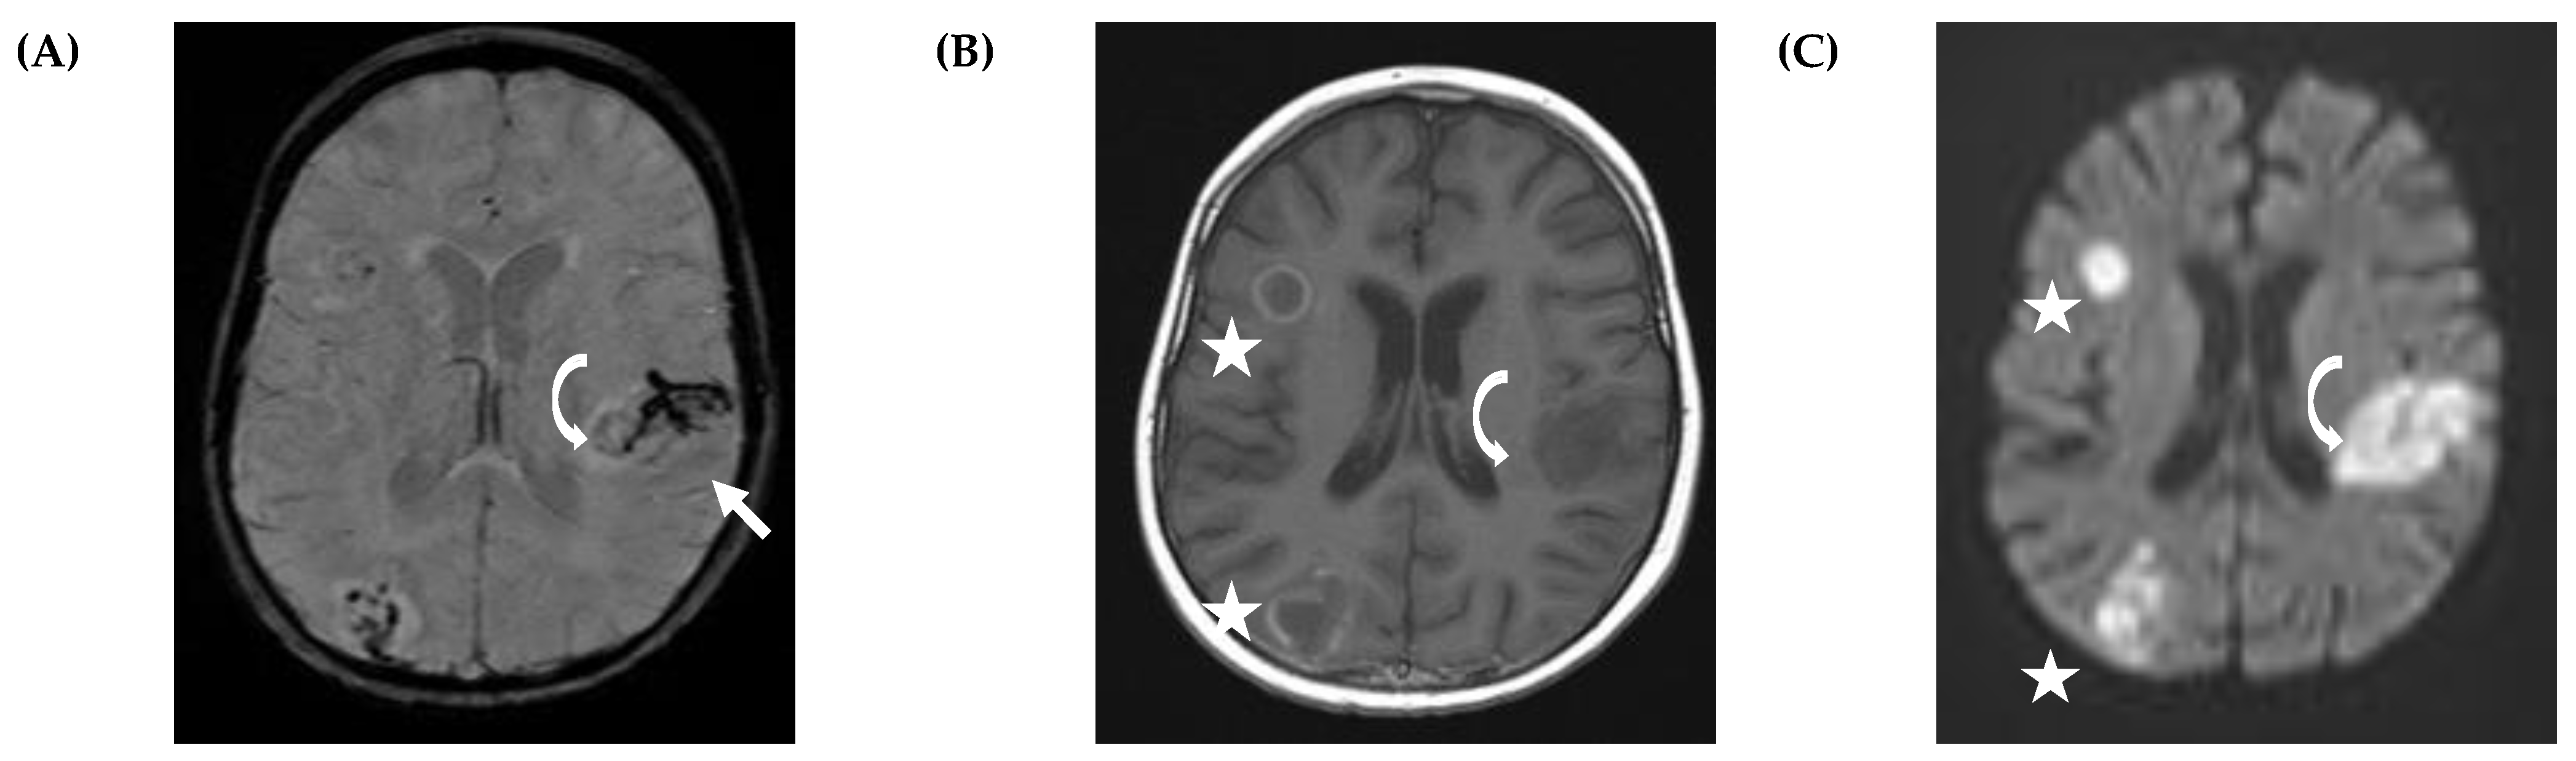

5.2. CNS Manifestations

- Antulov, R.; Dolic, K.; Fruehwald-Pallamar, J.; Miletic, D.; Thurnher, M.M. Differentiation of pyogenic and fungal brain abscesses with susceptibility-weighted MR sequences. Neuroradiology 2014, 56, 937–945. [Google Scholar] [CrossRef]

- Mathur, M.; Johnson, C.E.; Sze, G. Fungal infections of the central nervous system. Neuroimaging Clin. N. Am. 2012, 22, 609–632. [Google Scholar] [CrossRef]